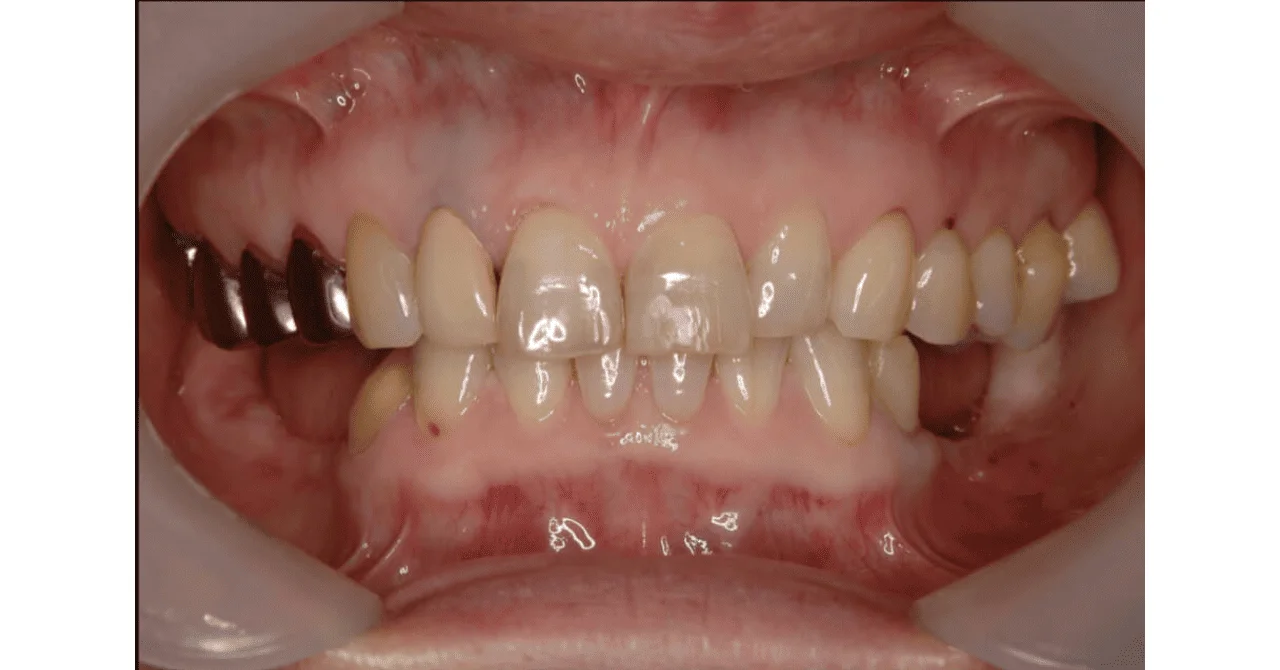

Before

After

前歯部のインプラント治療

約10ヶ月 / 630,300円(税込)リスク・副作用:GBR(骨造成)時に切開し人口骨を補填するため腫脹や疼痛を伴うことがある。 歯の間が狭いため、歯根にインプラントが触れる可能性がある。 (術前のシミュレーションで、インプラント埋入予定位置と横の歯との距離や角度を分析することで回避する)